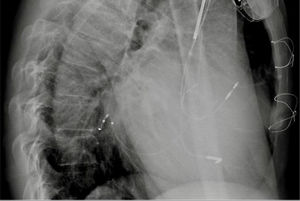

Via a subclavian vein approach, a 5F decapolar Response™ CSL electrophysiology catheter (Abbott) was used to create a three-dimensional (3D) model.1 After obtaining an endocardial shell the catheter was used to cannulate the coronary sinus (CS) (Figure 1). Under guidance by the electroanatomic system and very low dose fluoroscopy (to confirm that there was no catheter entanglement), a bipolar right ventricular (RV) lead was positioned in the RV apical septum. To continuously monitor the lead position (and identify possible lead dislodgment), the tip and ring poles were left connected to the EnSite system. The CS catheter was withdrawn and a sheath was used to catheterize the CS with the aid of the anatomic location on the 3D system. A guidewire (VisionWire; Biotronik) was inserted through the delivery system and connected to the EnSite system, and was used to map the anatomy and electrical activation of the CS branches (Figure 2). A branch was selected and the LV lead was placed in the latest site of ventricular activation (Figures 3 and 4). Using guidance by the navigation system and minimal fluoroscopy (hybrid approach), the right atrial lead was placed in a right appendage position, with real-time location of the other catheters (to check for possible displacement during manipulation of the atrial lead). Total procedure time was 96 min.